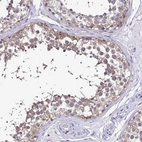

Immunohistochemical staining of human kidney shows moderate cytoplasmic positivity in cells in tubules.